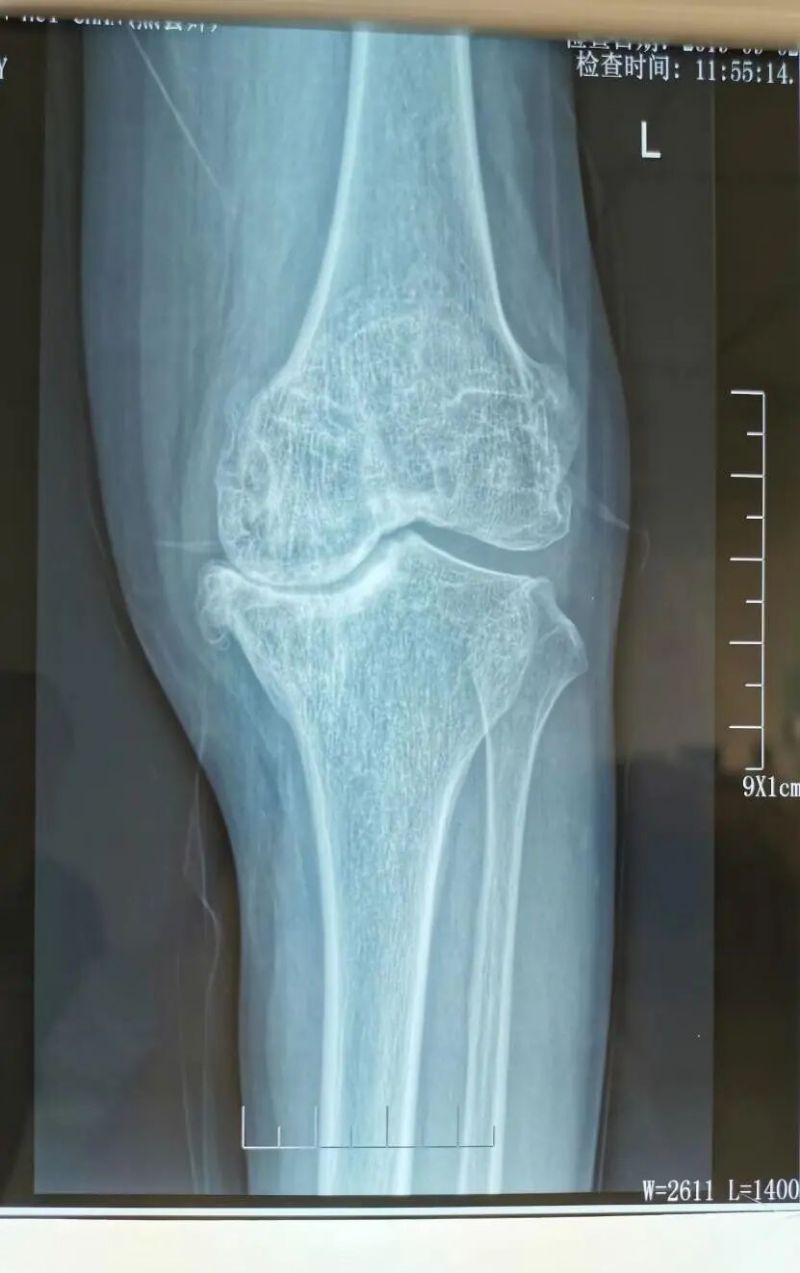

影像學(xué)檢查是診斷的重要手段。X線檢查就像給關(guān)節(jié)拍了一張“照片”,能夠清晰地顯示關(guān)節(jié)間隙變窄、骨質(zhì)增生、軟骨下骨硬化等典型表現(xiàn)。而MRI檢查則更像是一部“高清攝像機(jī)”,能更清晰地觀察關(guān)節(jié)軟骨、半月板、滑膜等軟組織的病變情況,為醫(yī)生提供更準(zhǔn)確的診斷依據(jù)。